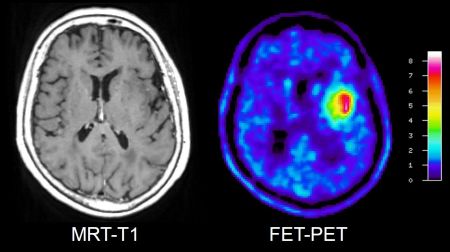

Diagnoseverfahren FET-PET: Erste Zulassung in der Schweiz

FET wird bei der Positronenemissionstomografie (PET) eingesetzt. Die FET-PET bietet im Vergleich zur üblichen radiologischen Diagnostik wichtige…